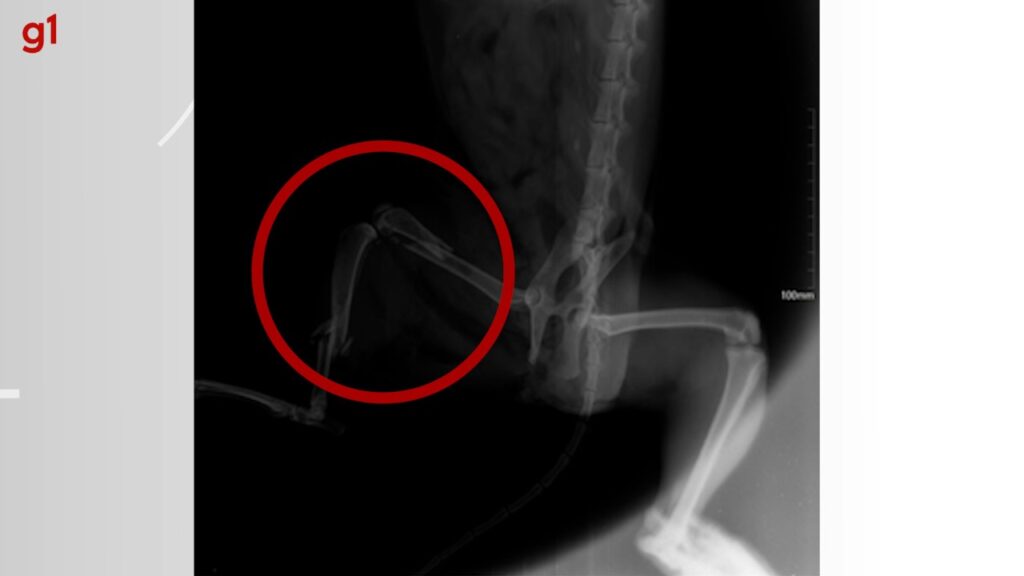

Tutora chegou a fazer vaquinha e empréstimo para pagar tratamento. Romeu sofreu duas fraturas e bala atravessou membro. Romeu levou um tira na perna direita e fraturou dois ossos

O gatinho Romeu morreu neste domingo (10), horas depois de passar por duas cirurgias. O felino teve a pata quebrada em dois lugares após ser atingido por um tiro que atravessou o membro. O caso aconteceu em Paraíso do Tocantins.

O gato, de três anos de idade, ficou em observação após passar pelas cirurgias e colocar placa em um dos ossos. Por conta dos machucados internos, Alessandra foi informada que as próximas 24 horas da recuperação de Romeu seriam decisivas.

Raio-x mostra fraturas do gato após levar um tiro na perna